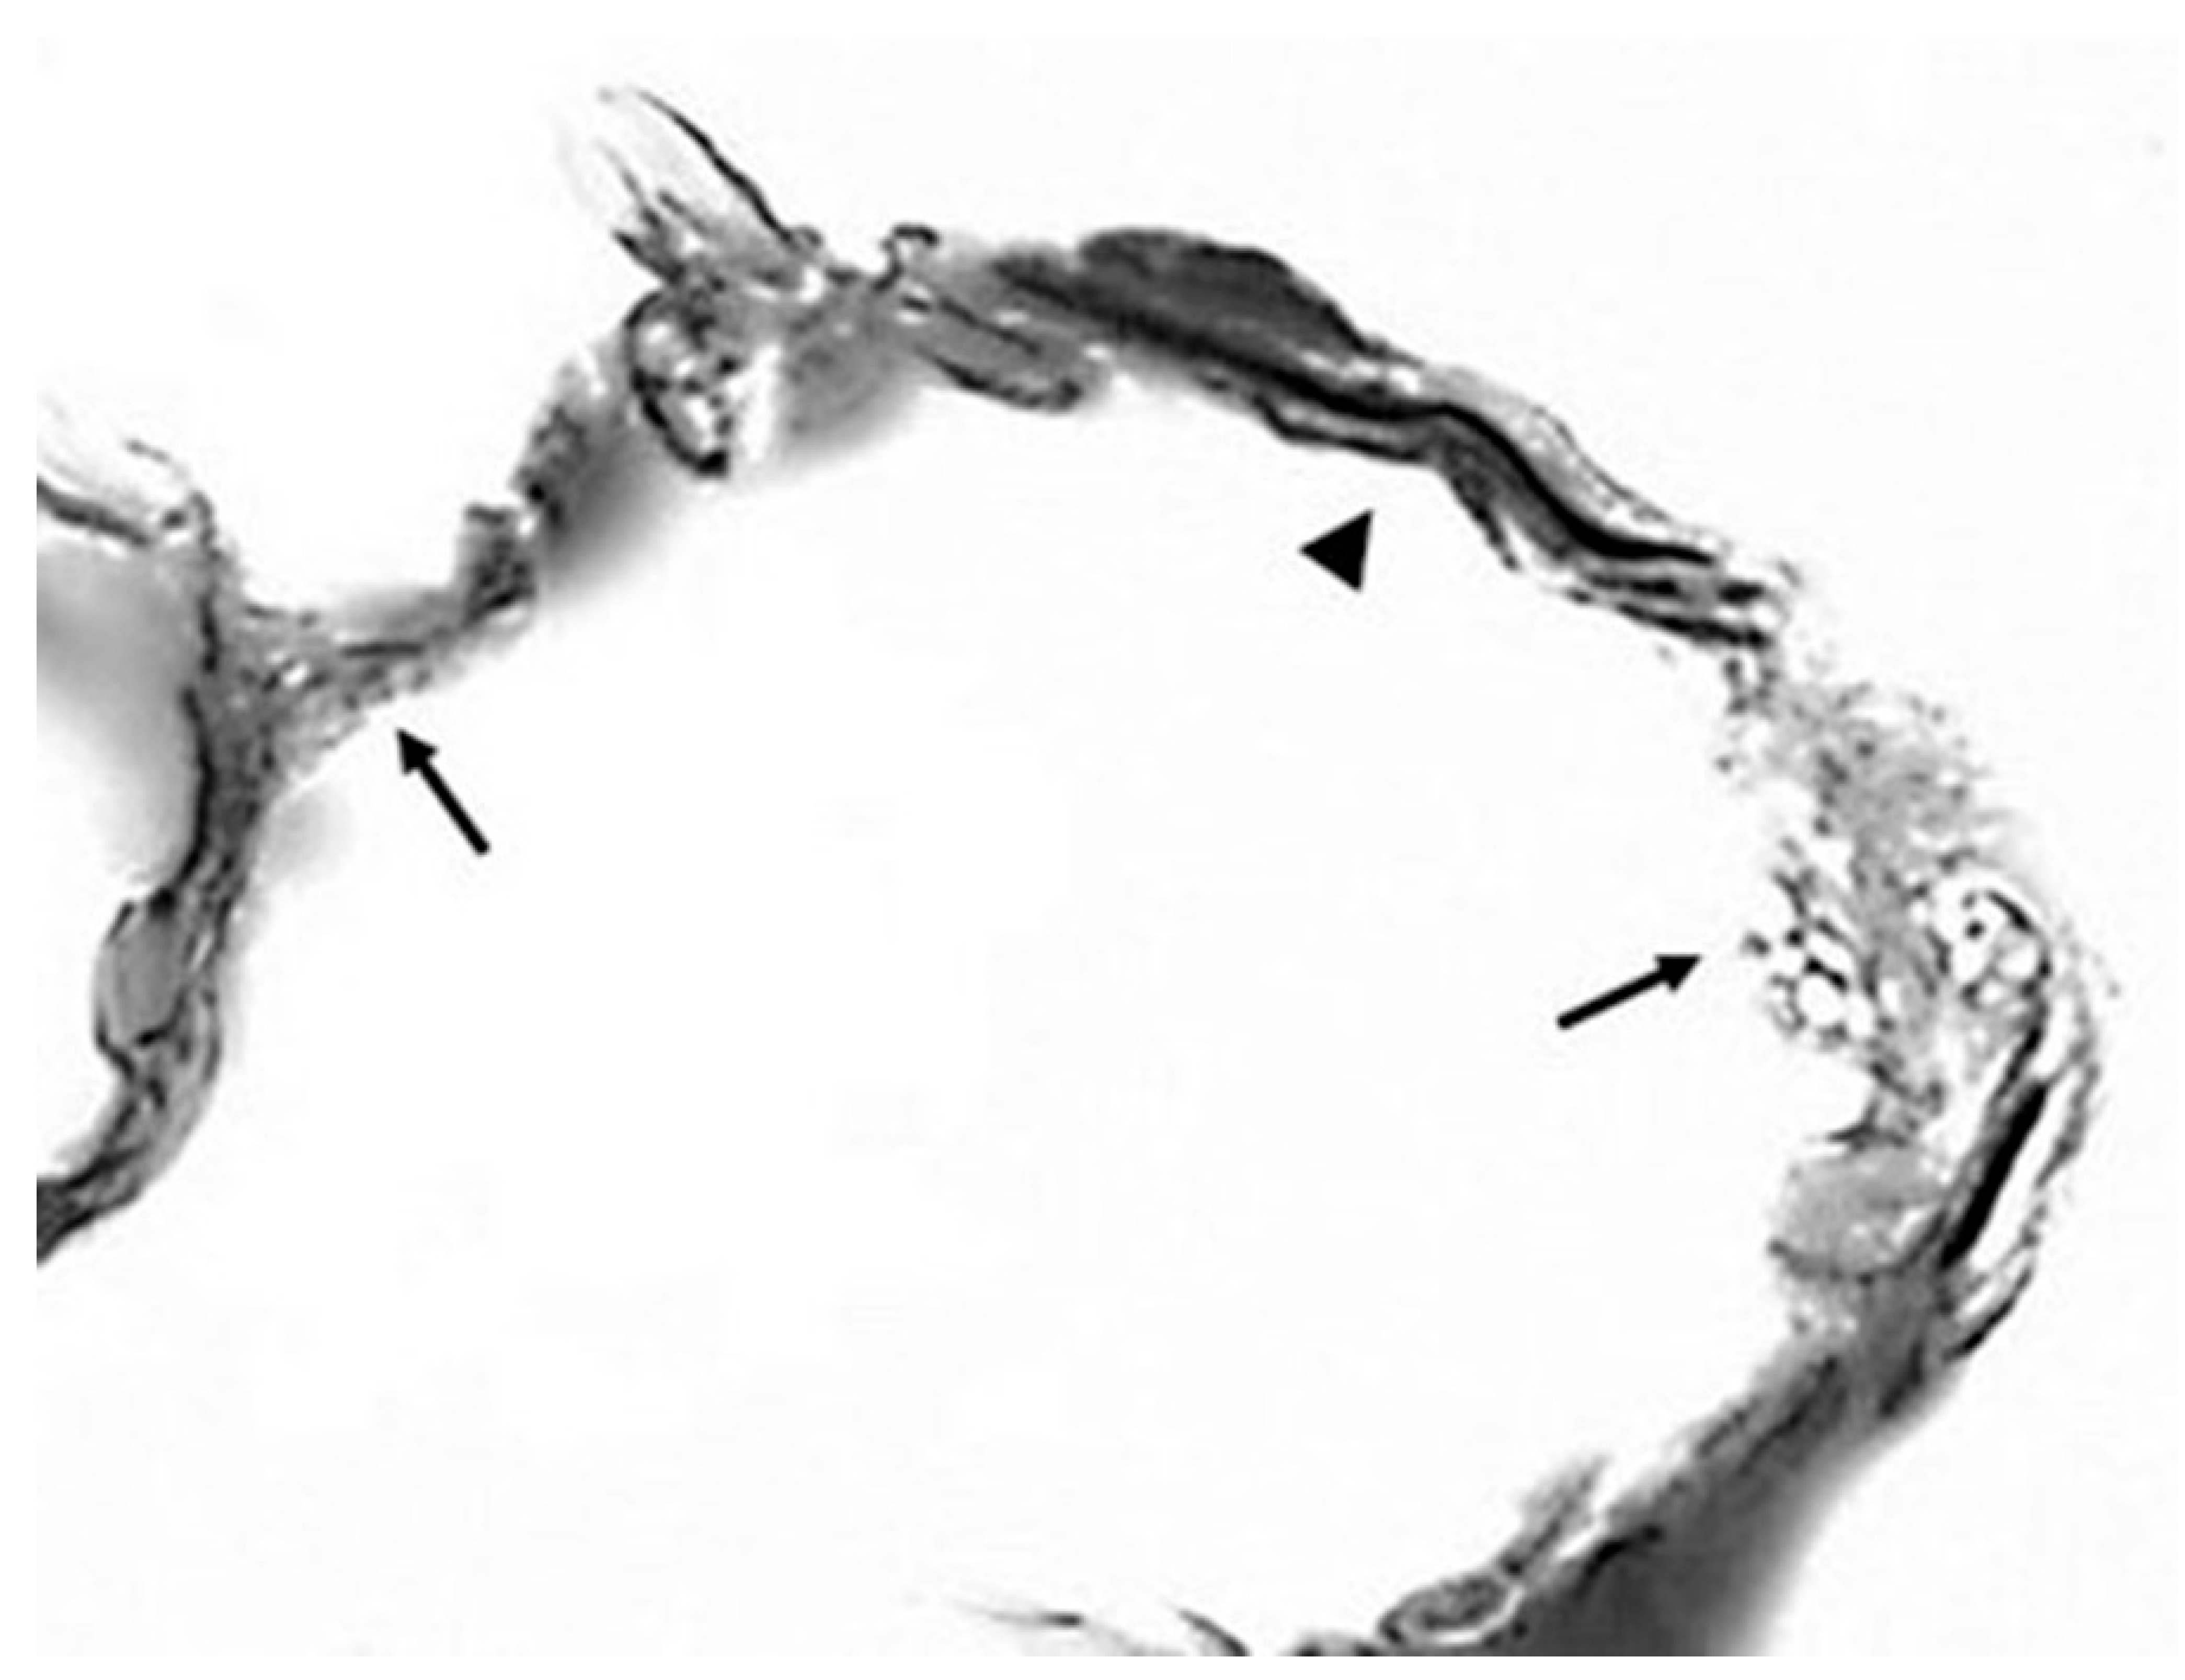

- Mehraban, S.; Gu, G.; Ma, S.; Liu, X.; Turino, G.; Cantor, J. The Proinflammatory Activity of Structurally Altered Elastic Fibers. Am. J. Respir. Cell Mol. Biol. 2020, 63, 699–706. [Google Scholar] [CrossRef] [PubMed] [PubMed Central]